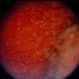

Choroidal Melanoma With Vitreous Seeding

Underlying retinal choroidal melanoma with dense vitreous seeding of choroidal melanoma cells.